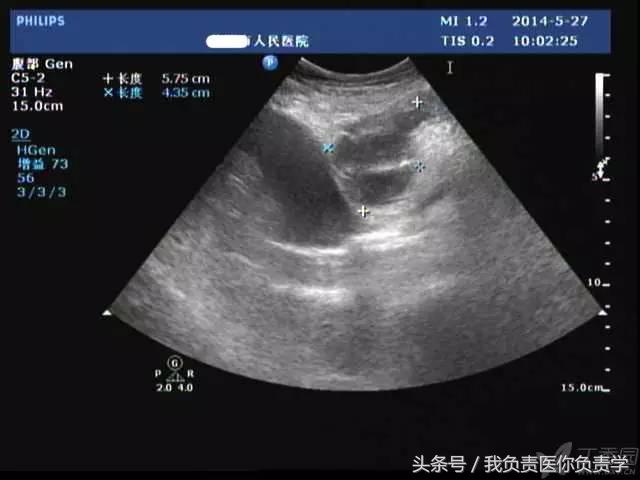

典型病例 2

(由丁香园注册用户「chengxiuyan_123」提供)

患者女,68岁,因上腹部痛 8天就诊 。超声检查发现胆囊体积明显增大,内部透声差,囊壁明显增厚,胆囊周围可见不规则分布的液性暗区。胆囊壁局部回声中断,探头加压及松开时,CDFI可见中断处出现因液体进出胆囊而导致的多普勒信号。患者行胆囊切除术,术后证实为胆囊穿孔。

图1示胆囊体积明显增大,内部透声差

图2示胆囊周围可见液性暗区分布

图3-图6示胆囊壁局部回声中断,探头加压及松开时CDFI可见红色及蓝色多普勒信号